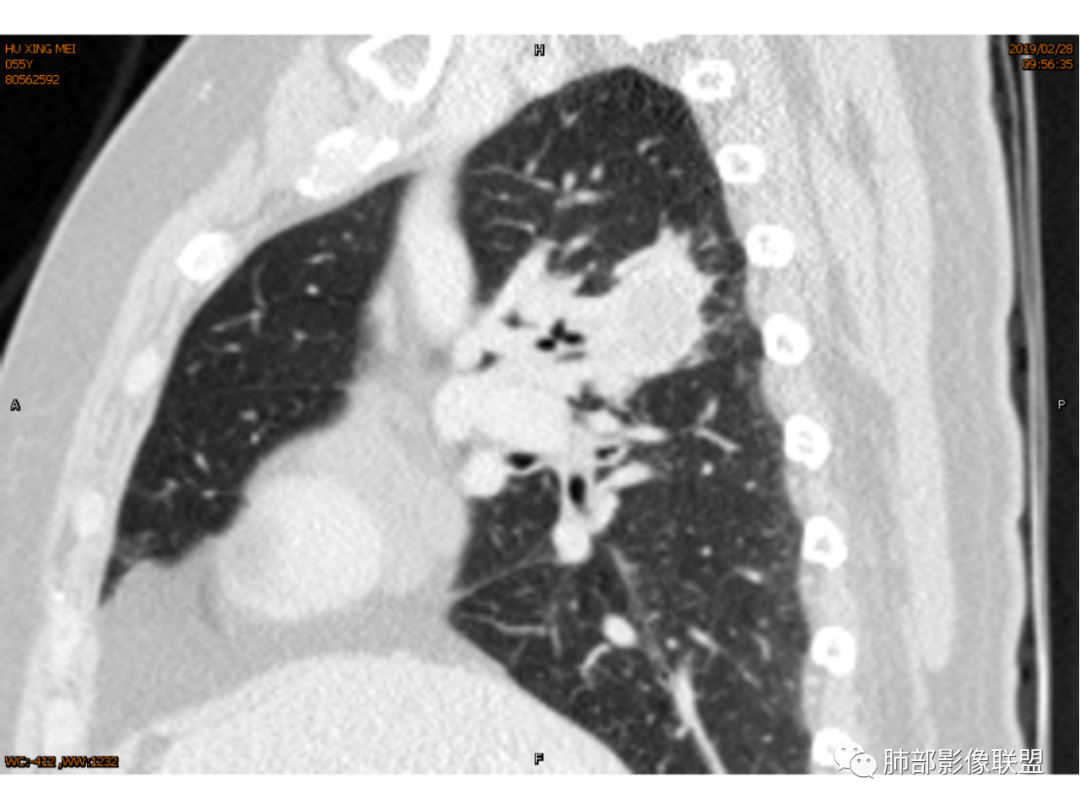

杨丽:老年女性,无肺气肿背景。右肺上叶后段胸膜下肿块,局部浅分叶,边缘见长软毛刺,支气管通入,临近叶间胸膜略增厚,增强扫描可见明显坏死,坏死边界清晰,壁较薄,其余病灶中等强化。纵隔小淋巴结。考虑:感染性病变,结核?鉴别囊肿伴感染。

寒江雪:椭圆形肿块,局部紧贴胸膜,软毛刺,纵隔淋巴结。强化壁薄、均匀。考虑炎性病变,结核?囊肿伴感染待排。

杨泽锋:病灶不大,坏死彻底,尽管卫星灶树芽征不明显(可能层厚太厚了),还是首先考虑TB

红星:咳嗽咳痰,痰中带血一个月。右肺上叶后段一个结节的阴影,分叶毛刺,肺门有淋巴结的肿大,CT值是软组织的密度。增强扫描中等程度的强化,见薄环状强化,病灶周围没有卫星病灶。首先考虑结核性的肉芽肿病变。鉴别诊断腺癌、结节病、淋巴瘤。

玫:咳嗽,咳痰,痰中带血一个月,肿瘤标志物不高,右肺上叶肿块影,边界清晰,浅分叶及少许毛刺,增强扫描病灶边缘呈环形强化,病灶内见坏死区,考虑结核可能,鉴别腺癌。

薏米:咳嗽,咳痰带血就诊,右肺上叶不规则密度增高影,未见支气管截断,边缘以凹陷收缩为主,环形强化,坏死边界清,坏死比较彻底,考虑结核,鉴别鳞癌、类癌。

王秀仙:右肺上叶后段结节,分叶,部分边缘平直部分膨隆,周围可见磨玻璃晕,密度不均,中心低密度坏死,增强薄环状强化,坏死界线较清楚,纵膈小淋巴结肿大,考虑肉芽肿性病变,结核。鉴别鳞癌。

傅昌瑜:女性,咳嗽咳痰痰中带血1月。血常规、肿瘤标记物正常。CT:右上叶后段类圆形结节,内侧紧贴纵隔,前与右主支气管后壁分界不清。外后部分边缘平直收缩、矢状位可见U型凹陷、桃尖征,周围见边缘模糊的GGO,软毛刺。右上叶后段支气管似乎变狭窄。增强呈薄壁环形强化,内部强化不明显,强化时边缘似见有多个小结节与主病灶融合(芋艿子?)。远端见细小结节。整体考虑炎性病变,结核可能性大,注意鉴别腺癌。

右肺上叶肿块,靠近脊柱,类圆形,部分层面周围有晕,平直、凹陷、膨隆均有,水平位未见明显分叶,失状位重建有棘突/毛刺?局部叶间胸膜增厚,无明显牵拉僵硬,支气管通畅;中心无明显强化,周围环形强化影。临床:女性,亚急性病程,咳血。考虑:倾向良性,结核?

1.女性,咳嗽咳痰痰中带血1月。血常规、肿瘤标记物正常。             2.CT示右肺上叶不规则肿块,边缘以平直收缩为主,可见U型凹陷及桃尖征,周围见边缘模糊的GGO,软毛刺,从形态学的角度病灶更支持炎性改变; 3.增强呈薄壁环形强化,壁光整、清楚,也支持炎性改变;病灶内部平扫CT值密度比较高,约40HU,明显高于水的密度,而且未见强化,提示病灶的坏死可能为凝固性坏死;    4.从上面的分析,病变更符合炎性,患者白细胞不高,治疗后没有好转,不支持普通细菌的感染;影像病灶较局限,边界较清楚,病灶慢性炎症或肉芽肿,形态机发病部位更符合继发性肺结核。患者非易感人群,病灶孤立,尽管有液化,也很难第一时间考虑真菌,尤其是曲霉菌感染。什么是炎性肉芽肿?炎性肉芽肿的常见疾病谱系有哪些?那什么是凝固性坏死和干酪样坏死?跟一般的液化性坏死有什么区别?接下来我们逐一学习一下。